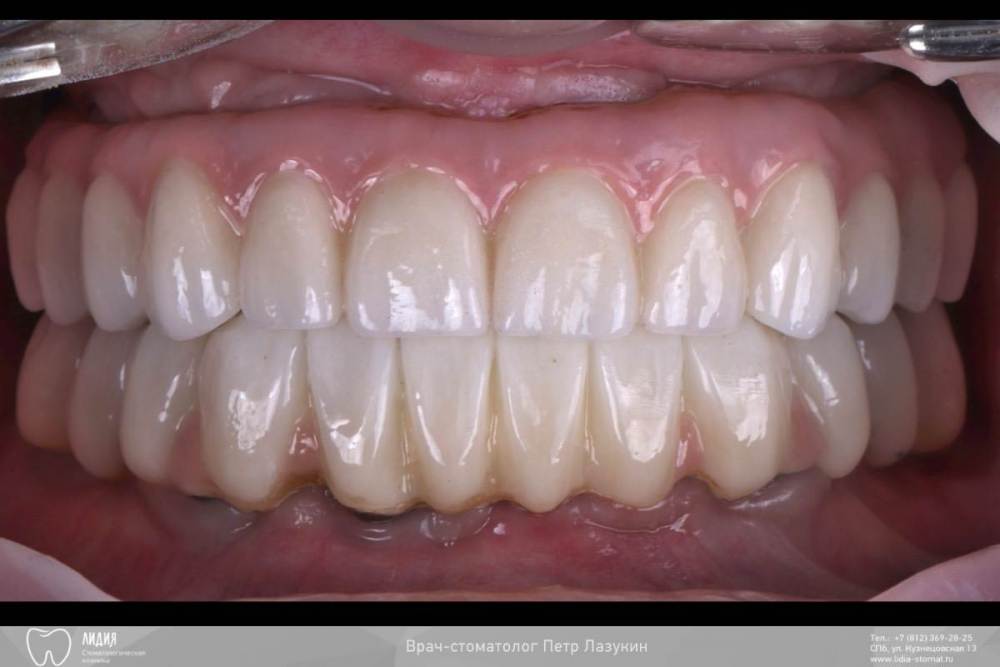

pit Опубликовано 9 августа, 2023 Поделиться Опубликовано 9 августа, 2023 Всем привет! Клинический случай тотального протезирования с опорой на имплантаты. Немедленная имплантация верхней и нижней челюсти с интервалом в 2 месяца. На верхней челюсти редукция, имплант 25 зуба транссинус. Отсроченная нагрузка, так как треснул гребень. Видео операции здесь https://youtu.be/YZM-A8we1WQ Постоянное протезирование ДЦ коронками с тирановыми каркасами. Верх с уровня МЮ, низ с уровня платформ. 2.mov 7 1 3 Ссылка на комментарий